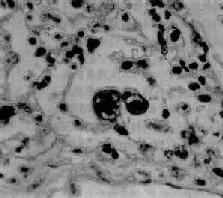

图9-21 腺病毒肺炎

图中央可见肿大肺泡上皮细胞中的核内包含体